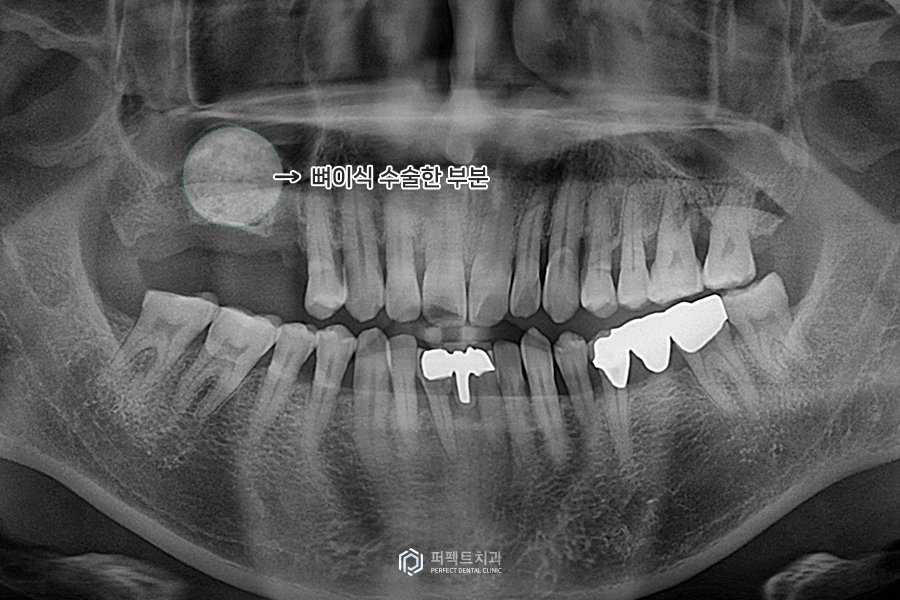

상악동 수술 후 은 파노라마 사진을 보시면 전에는 1~2mm정도의 뼈가 있었는데 비어있던 부분이 하얗게 뼈로 채워진 것을 볼 수 있습니다. 화면을 보시면 긴 임플란트를 심어도 후에 공간이 남을 정도로(약 15mm) 성공적인 뼈이식 결과를 얻을 수 있었습니다. 이제 후에 뼈가 굳으면 임플란트를 식립하면 됩니다.